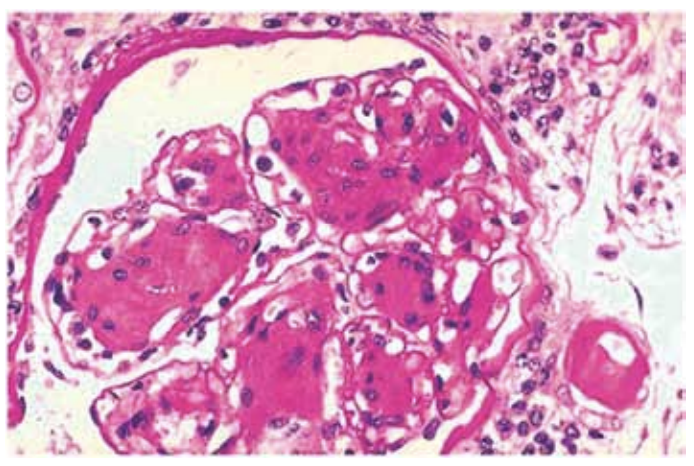

Homem, 54 anos, diagnóstico de diabetes mellitus há

4 anos, desconhecia o valor de sua glicemia antes do

diagnóstico. Na consulta inicial, negou antecedentes patológicos. Exame físico: PA 135 x 80 mmHg e edema de

membros inferiores ++/4. Exame de fundo de olho normal. Exames recentes: creatinina sérica = 1,3 mg/dL;

exame de urina: proteína +++/4, hemácias = 80.000/mL

(VR até 10.000), leucócitos = 8.000/mL (VR até 10.000);

proteinúria 3,8 g/24horas; albumina sérica 3,1 g/dL. Realizada biópsia renal, na qual foi identificada a seguinte

lesão glomerular na microscopia óptica:

(Arquivo pessoal; imagem usada com autorização)

Em face do exposto, assinale a alternativa correta.